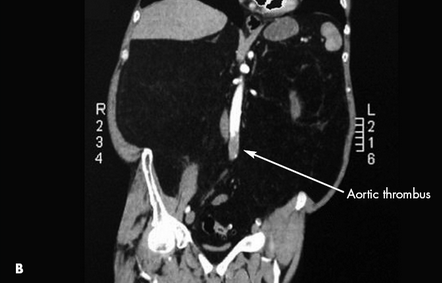

CT scans showed both a pulmonary embolus (A) and a thrombus in the wall of the abdominal aorta (B). Anticoagulation therapy was initiated. A Doppler study showed a left lower extremity deep venous thrombus. Further evaluation with transesophageal echocardiography showed a patent foramen ovale (C) and an interatrial aneurysm, with a positive bubble study.* The patient had no known history of either condition. Because of the patent foramen ovale, thrombi had traveled not only to the lungs but also to the aorta. This likely caused the spinal ischemia and paraparesis.